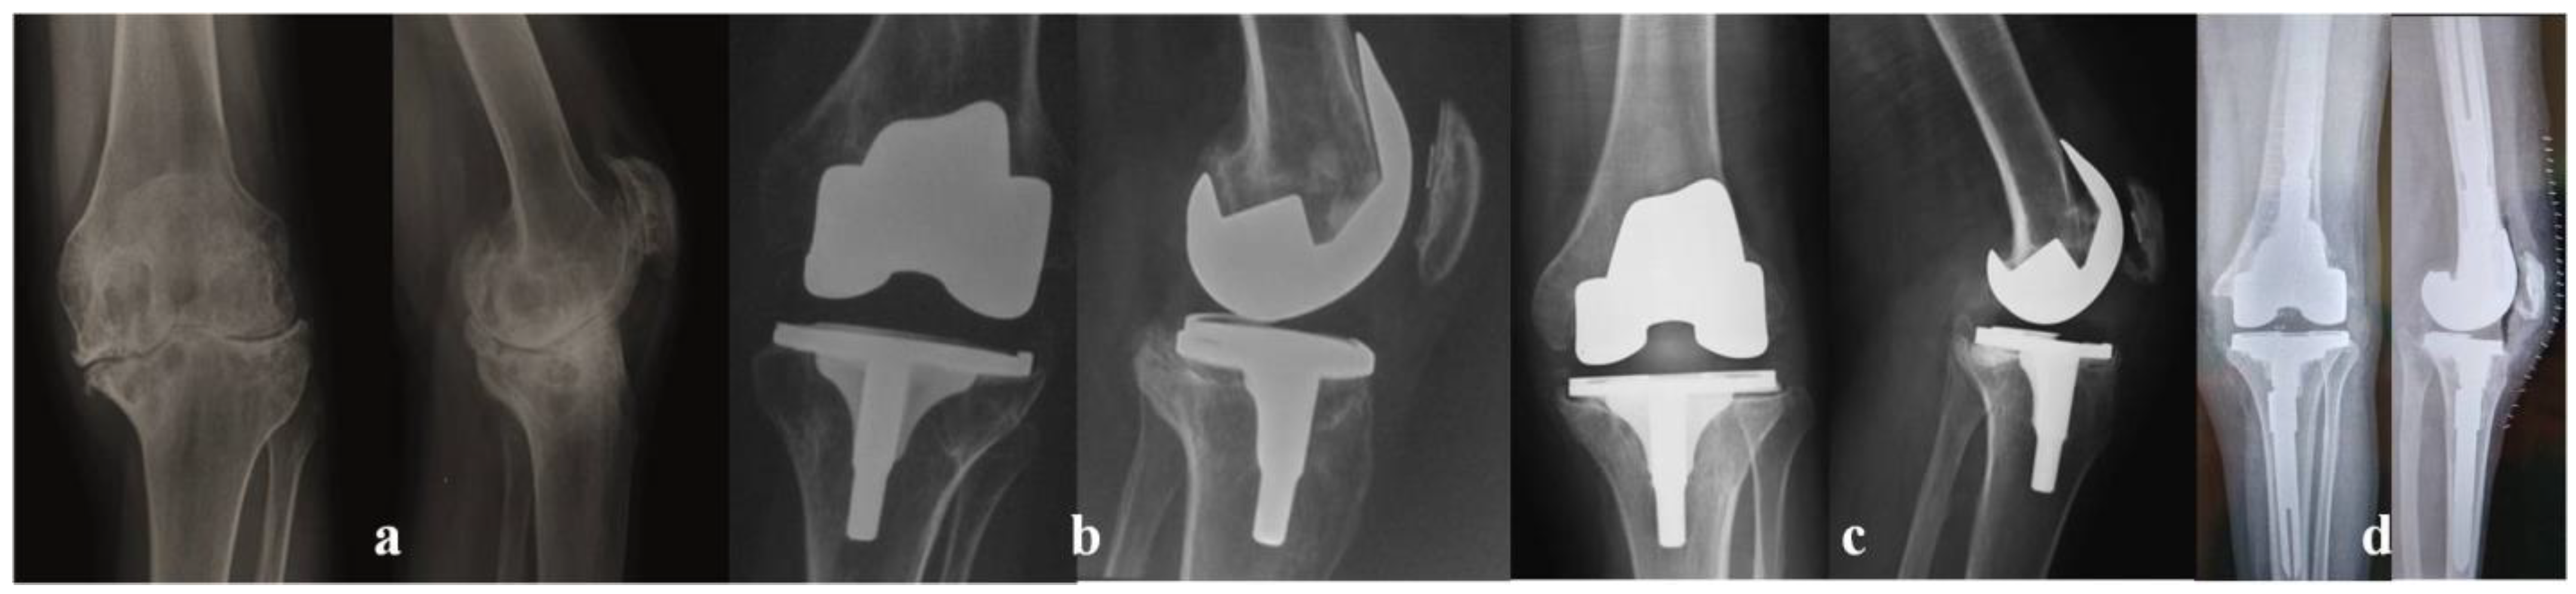

- Innocenti, M.; Matassi, F.; Carulli, C.; Nistri, L.; Civinini, R. Oxidized zirconium femoral component for TKA: A follow-up note of a previous report at a minimum of 10 years. Knee 2014, 21, 858–861. [Google Scholar] [CrossRef]

- Civinini, R.; Matassi, F.; Carulli, C.; Sirleo, L.; Lepri, A.C.; Innocenti, M. Clinical Results of Oxidized Zirconium Femoral Component in TKA. A Review of Long-Term Survival. HSS J. 2017, 13, 32–34. [Google Scholar] [CrossRef]

- Innocenti, M.; Civinini, R.; Carulli, C.; Villano, M.; Linari, S.; Morfini, M. A modular total knee arthroplasty in haemophilic arthropathy. Knee 2007, 14, 264–268. [Google Scholar] [CrossRef]

- Carulli, C.; Innocenti, M.; Linari, S.; Morfini, M.; Castman, G.; Innocenti, M. Joint replacement for the management of haemophilic arthropathy in patients with inhibitors: A long-term experience at a single Haemophilia centre. Haemophilia 2020, 27, e93–e101. [Google Scholar] [CrossRef]